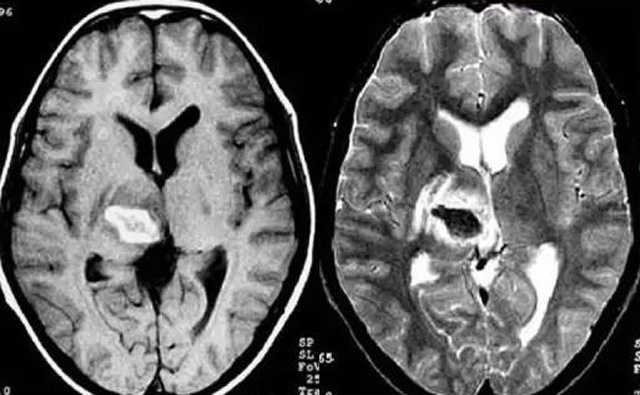

發(fā)現(xiàn)病人出血腦梗相關(guān)癥狀時候第一時間就醫(yī),需要攜帶以往的影像檢查資料。向醫(yī)生提供相關(guān)的病史基本資料。做影像檢查時候需要全身不攜帶金屬物品。檢查時候身體保持不動,不然偽影對檢查結(jié)果有干擾。磁共振MRI發(fā)現(xiàn)缺血性卒中后,幫助進(jìn)一步查找病因。由于CT上小腦跟腦干顱骨影響,容易導(dǎo)致漏診。MRI檢查可以對CT檢查不足的補(bǔ)充。短暫的腦缺血TIA也需要進(jìn)行影像檢查。短暫性缺血一般10幾分鐘后好轉(zhuǎn)。檢查目的可以確定TIA的病因。降低腦梗死的發(fā)生率。磁共振有助于排出TIA表現(xiàn)的顱內(nèi)病變,有診斷及時治療的價值。磁共振MRI檢查時間比較長,不太適合急診病人。但是可以發(fā)現(xiàn)腦干小腦的出血問題。因?yàn)榧毙阅X梗死的早期和急性期,缺血區(qū)的腦組織還沒有完全壞死,頭顱CT不能顯示病灶,所以就需要MRI磁共振檢查,這個對陳舊跟亞急性出血顯示比較好。缺點(diǎn)性價比不高,費(fèi)用比較貴。頭顱的磁共振MRI在發(fā)病后的幾天CT的敏感降低時候發(fā)揮大作用。,MRI可作為診斷蛛網(wǎng)膜下腔出血和了解破裂動脈瘤部位的一種重要方法,必要時進(jìn)一步進(jìn)行DSA檢查,幫助制訂臨床的手術(shù)治療方案,